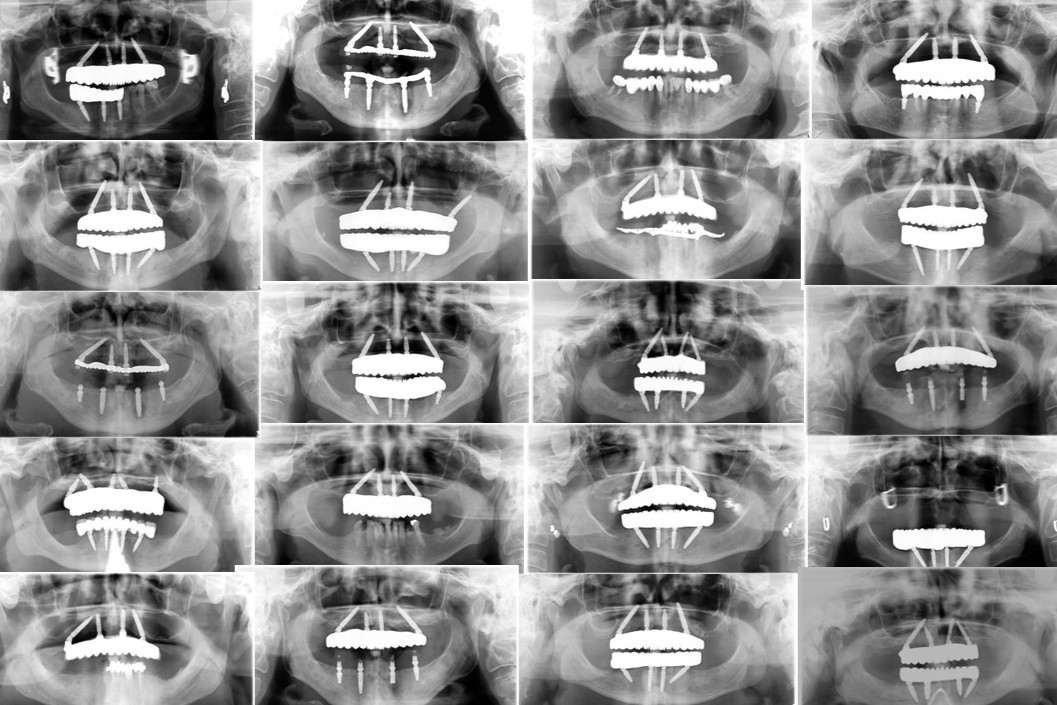

The Fallacy of “All-on-X”: Why Protocol Trumps Implant Count

The evolution of full-arch rehabilitation has transitioned from “The more, the merrier” approach of the 1990s and early 2000s to the sophisticated biomechanics of the Graft Free Implantology movement. Historically, treating implants as direct analogs for natural roots led to catastrophic failures. High implant density compromised blood supply and violated the necessary 3mm biological width…